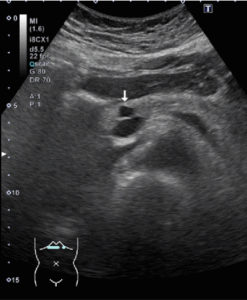

*膵のう胞の腹部エコー画像

膵臓の内部に黒いしこりとして観察されます。